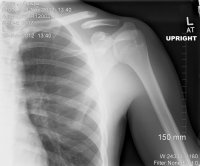

I expressed my opinion of that, and now we have a trauma surgeon appointment in 2 weeks.